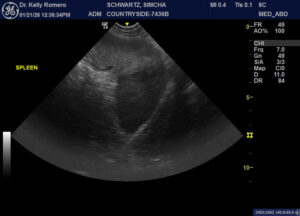

10 yr FS Shep cross with lethargy, weakness and dec. appetite. Concern for the hypoechoic splenic head. Could see vessels on doppler, but think they were attenuated to those in the body. Patient was not painful during the exam. FNAs of the spleen, irregular liver (nodular) and the hypoechoic cranial abdominal lesion shown in the last video are pending. Regarding the latter, no fluid obtained when aspirating other than for slide. Lesion ventral to the stomach and caudal to the liver, not in the region of the pancreas. How worried re spleen blood flow while aspirates pending?

splenic infarct, necrosis/abscess or sarcoma are my main diffs./ If nowhere else it needs to come out

Thank you, Eric. I need to confirm w/ referring vet, but owner thought the aspirates came back as sarcoma